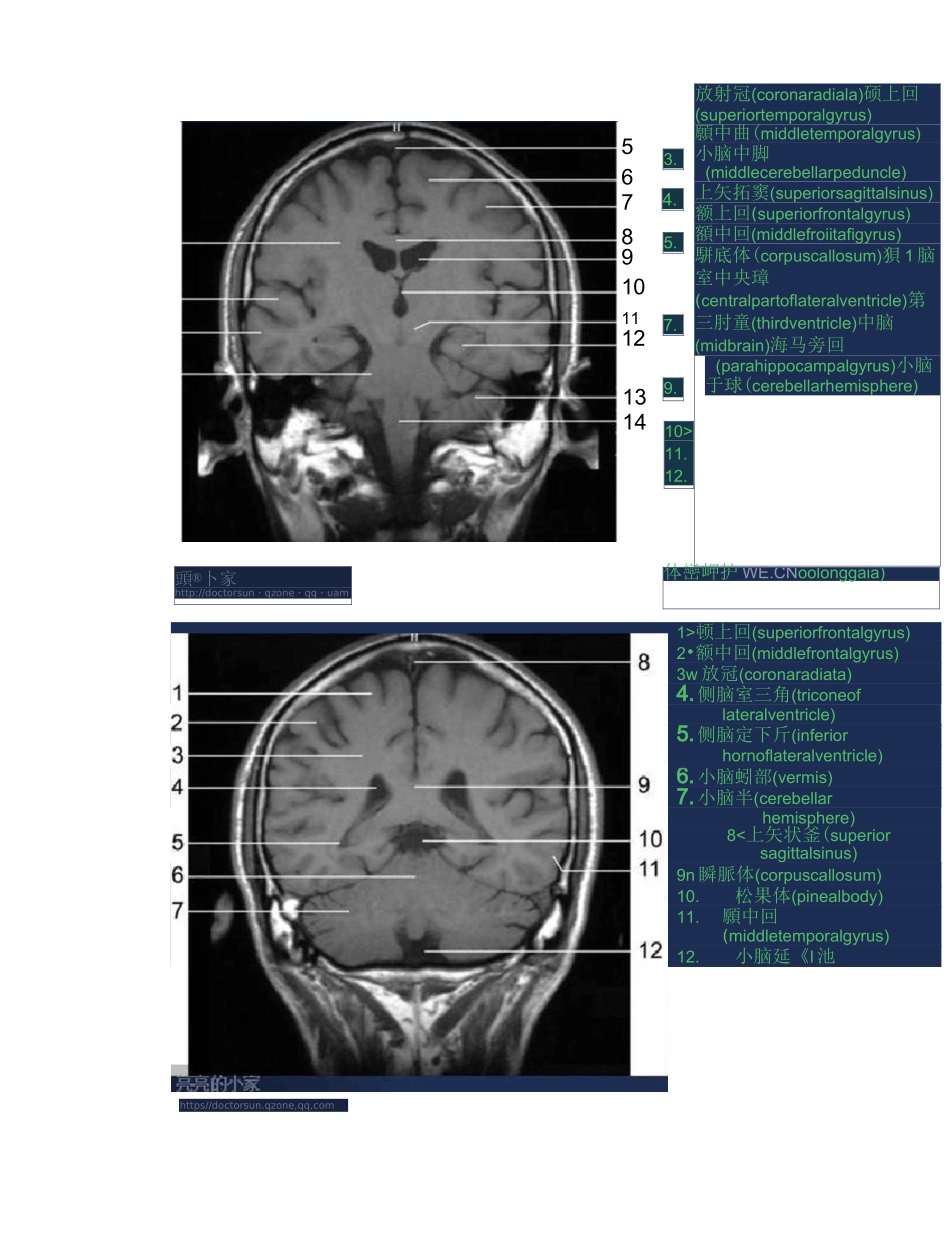

全身 MRI 图谱12.上頓寞(muHlary*inuft)整釧璋 FKttp^/d^ct^ruu 怕■屜 GW 靳qqwn8910rJ67仏鼻中驕(nasalseptum)2.*鼻甲(middleconcha>3.延謄体(adiposebodyoforbit)4.鼻外肌(lateralptergoid)5•顔肌(temporalis}6.理寞(Ephenoidalsinus)I.三戈神经节(trigEEiwtganglion)8«基底动蘇(basilara.)9,A&flL(medLIIIdobkngata>勺队小(cerebellarhemisphere)II.厳肯岩娜(petrousp^rtoftemporalbone)霸內卜家http:/^dactarE-un.qzgnE.qgFcearnN3.10111213氐6・7.8.9,鑽上倒(stipBriarfrontalgyrus)并攵射局(coronaradiatat 中夬都顿上回(superiorfrontalgyrus)2•额中回(middlefrontalgyrus)3w 放冠(coronaradiata)4.侧脑室三角(triconeoflateralventricle)5.侧脑定下斤(inferiorhornoflateralventricle)6.小脑蚓部(vermis)7.小脑半(cerebellarhemisphere)8<上矢状釜(superiorsagittalsinus)9n 瞬脈体(corpuscallosum)10.松果体(pinealbody)11.願中回(middletemporalgyrus)12.小脑延《l 池https//doctorsun.qzone,qq,com頭®卜家http://doctorsun・qzone・qq・uam5678910111213143.4.5.7.9.10>11.12.放射冠(coronaradiala)硕上回(superiortemporalgyrus)願中曲(middletemporalgyrus)小脑中脚(middlecerebellarpeduncle)上矢拓窦(superiorsagittalsinus)额上回(superiorfrontalgyrus)額中回(middlefroiitafigyrus)駢底体(corpuscallosum)狽 1 脑室中央璋(centralpartoflateralventricle)第三肘童(thirdventricle)中脑(midbrain)海马旁回(parahippocampalgyrus)小脑于球(cerebellarhemisphere)体巒岬护 WE.CNoolonggaia)MEDLI2>3.5.6>7>8、眼球(eyeball)视神经(opticalnerve)彦肌10.小脑蚓部(vermis)*14、直窦(straightsinus)12M 横婁(transversesinus)*13、,卜脑半球(cerebellarhemisphere)*14、第四脑室(fourthventricle)45、基•庶^动脉 AB|i16.顯叶(t©1.(eyeball)2.鼻中隔(nasalseptum)3.眶脂体(adiposebodyoforbit)4.瀬肌(temporalis)5.题下回(interiortomporalgyrus)6.三又神经节(tiigeminzlganglion)7M 縣...